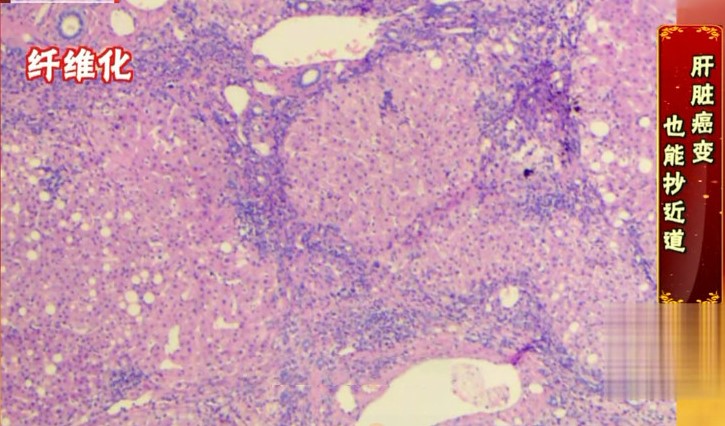

3)肝纤维化

进入肝纤维化期,肝细胞重复的坏死修复,形成疤痕,开始出现肝纤维化,肝细胞减少,肝纤维组织增多,指标异常的同时出现一系列症状,走到这一步就很难逆转了,我们能做的就是不让它再进一步往肝硬化、肝癌发展。